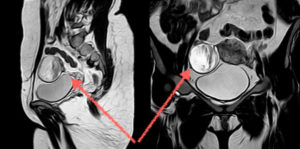

- Ректо-абдоминальное и влагалищно-абдоминальное обследование гинеколога. Двуручный осмотр позволяет определить округлое образование спереди или сбоку от матки.

- УЗИ малого таза с использованием трансвагинального или трансабдоминального датчика. Данный метод диагностики сегодня признан одним из самых информативных: при проведении УЗИ можно определить точные размеры кисты, плотность ее содержимого и толщину ее капсулы. С помощью метода ЦДК (цветного доплеровского картирования) можно точно определить, является ли новообразование злокачественным или доброкачественным: способ помогает оценить характер кровотока (его отсутствие).

- Дермоидная киста яичника мрт — данная процедура позволяет в случае сомнений подтвердить диагноз: во время МРТ жировая ткань зрелой тератомы становится различимой.

- Лапароскопию: дермоидная киста яичника лапароскопия – это получение снимка кисты при помощи эндоскопа, введенного через маленький разрез в полость живота.

Дермоидная киста яичника обычно имеет круглую или овальную форму, гладкие наружные стенки, может вырастать диаметром до 15 сантиметров.

Причины формирования зрелых тератом неизвестны; в их развитии предполагается провоцирующая роль гормональных изменений в период полового созревания и климакса, травм живота. Дермоидные кисты яичника растут медленно, обычно имеют одностороннюю локализацию (чаще правостороннюю).